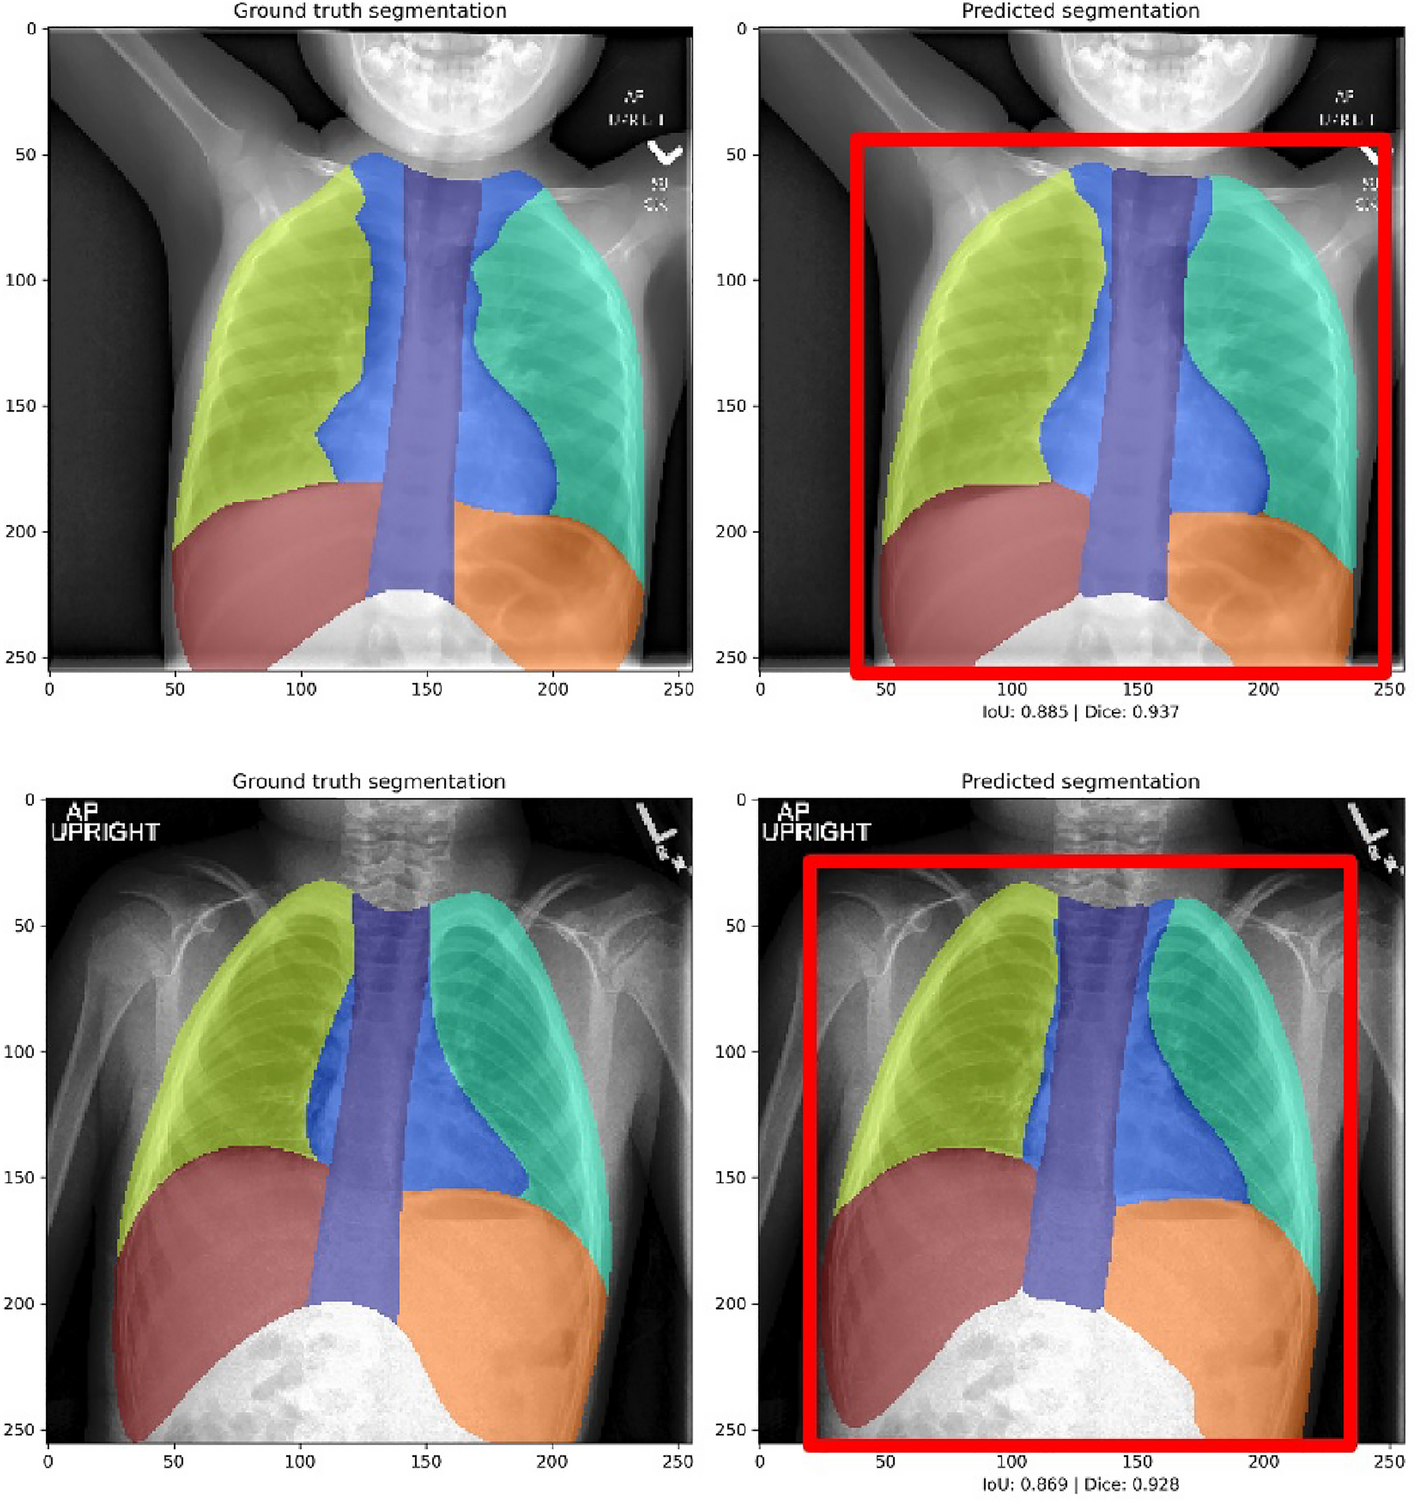

Figure 2

Representative results from multi-class segmentation showing manually labeled images (left) and U-Net results (right) with final automatically-generated cropped region represented by red box.